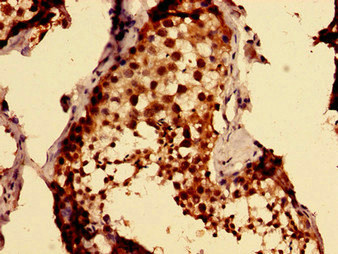

Immunohistochemistry of paraffin-embedded human testis tissue using CSB-PA872420LA01HU at dilution of 1:100